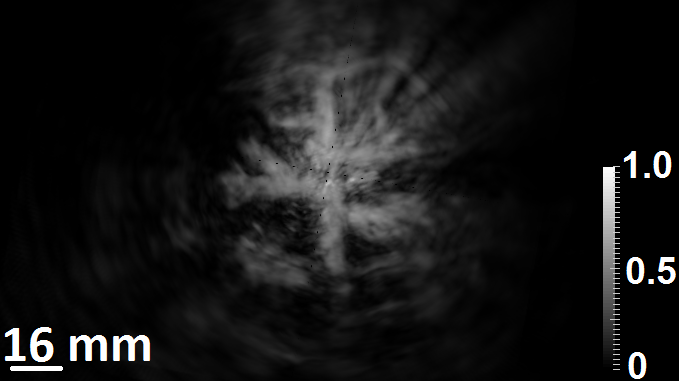

7.2 Experimental studies: Results

The images reconstructed from the experimental data are shown in  Fig. 8.  Figs. 8a, 8b and 8c displays the image reconstructed by application of superscript\mathbb{H}^{\dagger}, while the image reconstructed by use of the BP algorithm is shown in  Figs. 8d, 8e and 8f. In the BP reconstruction algorithm, the longitudinal speed of sound of the background fluid media was set to be 1.507 mmμsmm𝜇s\frac{\text{mm}}{\mu\text{s}}.

Figure 8: The reconstructed initial pressure distribution using superscript\mathbb{H}^{\dagger} along three different views are shown in (a)-(c).The reconstructed initial pressure distribution using BP algorithm along three different views are shown in (d)-(f).The reconstructed initial pressure distribution using μ=0superscriptsubscript𝜇0\mathbb{H}_{\mu=0}^{\dagger} along three different views are shown in (g) -(i).

These results demonstrate that the superscript\mathbb{H}^{\dagger} can more effectively mitigate image distortions due to acrylic globe (i.e., simulated skull structure) than can the BP algorithm. Additionally, some of the smaller vessel structures are not identifiable in the BP image but are present in the image reconstructed by use of superscript\mathbb{H}^{\dagger}.

The image reconstructed by use of μ=0subscriptsuperscript𝜇0\mathbb{H}^{\dagger}_{\mu=0} is shown in Figs. 8g, 8h and 8i. This image contains dramatically elevated artifact levels as compared to the one reconstructed by use of superscript\mathbb{H}^{\dagger}, shown in Figs. 8a, 8b and 8c. This again demonstrates that neglecting to model the elastic properties of the medium can lead to significant deterioration in image quality.